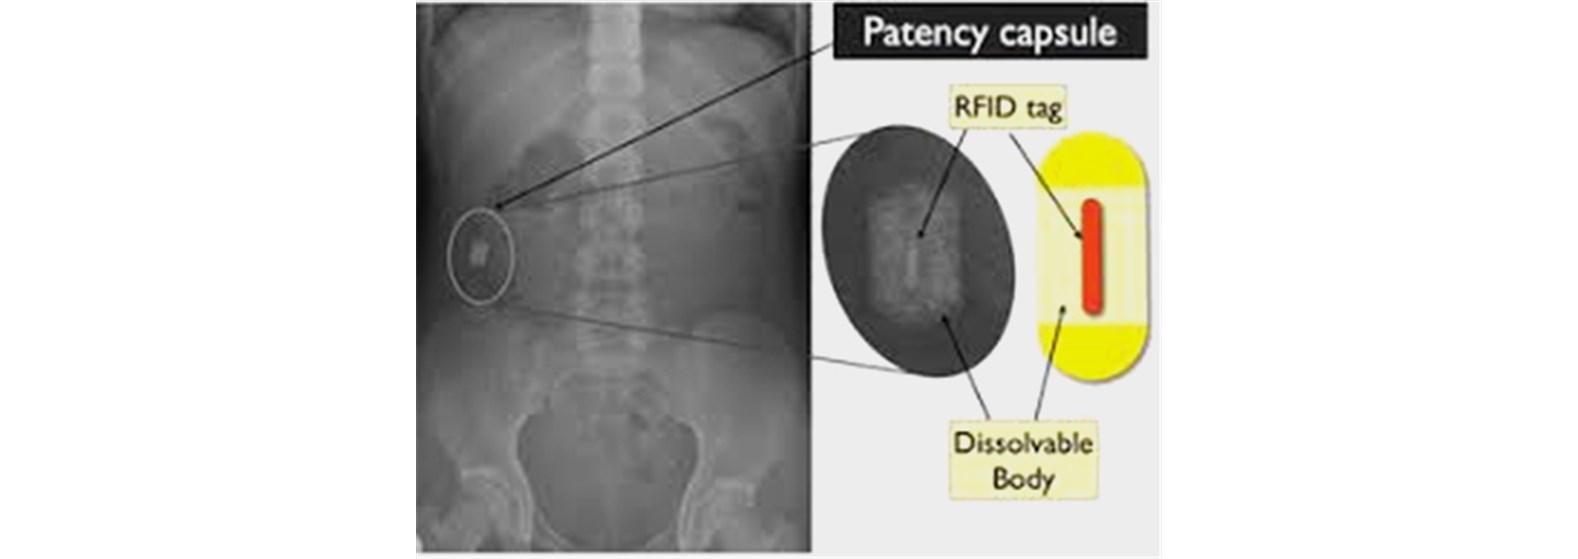

הקפסולה היא פעולה בטוחה למדי, עם סיבוכים נדירים מאוד. הסיבוך השכיח ביותר הוא היתקעות הקפסולה במעי הדק. סיבוך זה עלול להתרחש בתדירות שבין 1 ל-100 לבין 1 ל-2000 מקרים, כתלות בהתוויה לבדיקה. במרבית מקרי ההיתקעות, לא מופיעים תסמינים כלשהם ולעיתים הגלולה יכולה להיפלט עצמאית כעבור ימים או שבועות. במידה וזה לא קרה, או במידה ומופיעים תסמיני היתקעות (בחילות , הקאות, כאבי בטן), ניתן לשלוף את הקפסולה באמצעות פעולה אנדוסקופית או ניתוח. מטופלים לאחר ניתוחים בטניים, הקרנות לבטן ועם מחלת קרוהן מפושטת במעי הדק, נמצאים בסיכון מעט מוגבר. במטופלים בסיכון נהוג לבצע קפסולת דמה (patency) לפני שימוש בקפסולה אבחנתית. קפסולת הדמה היא גלולה נטולת מצלמה שכוללת גוף מסיס ורכיב שניתן לגלות על ידי משדר אלחוטי או צילום רנטגן.

במידה וקפסולת הדמה עוברת את המעי בהצלחה ומבלי להיתקע, הסיכוי להיתקעות הגלולה המצלמת נמוך ביותר.